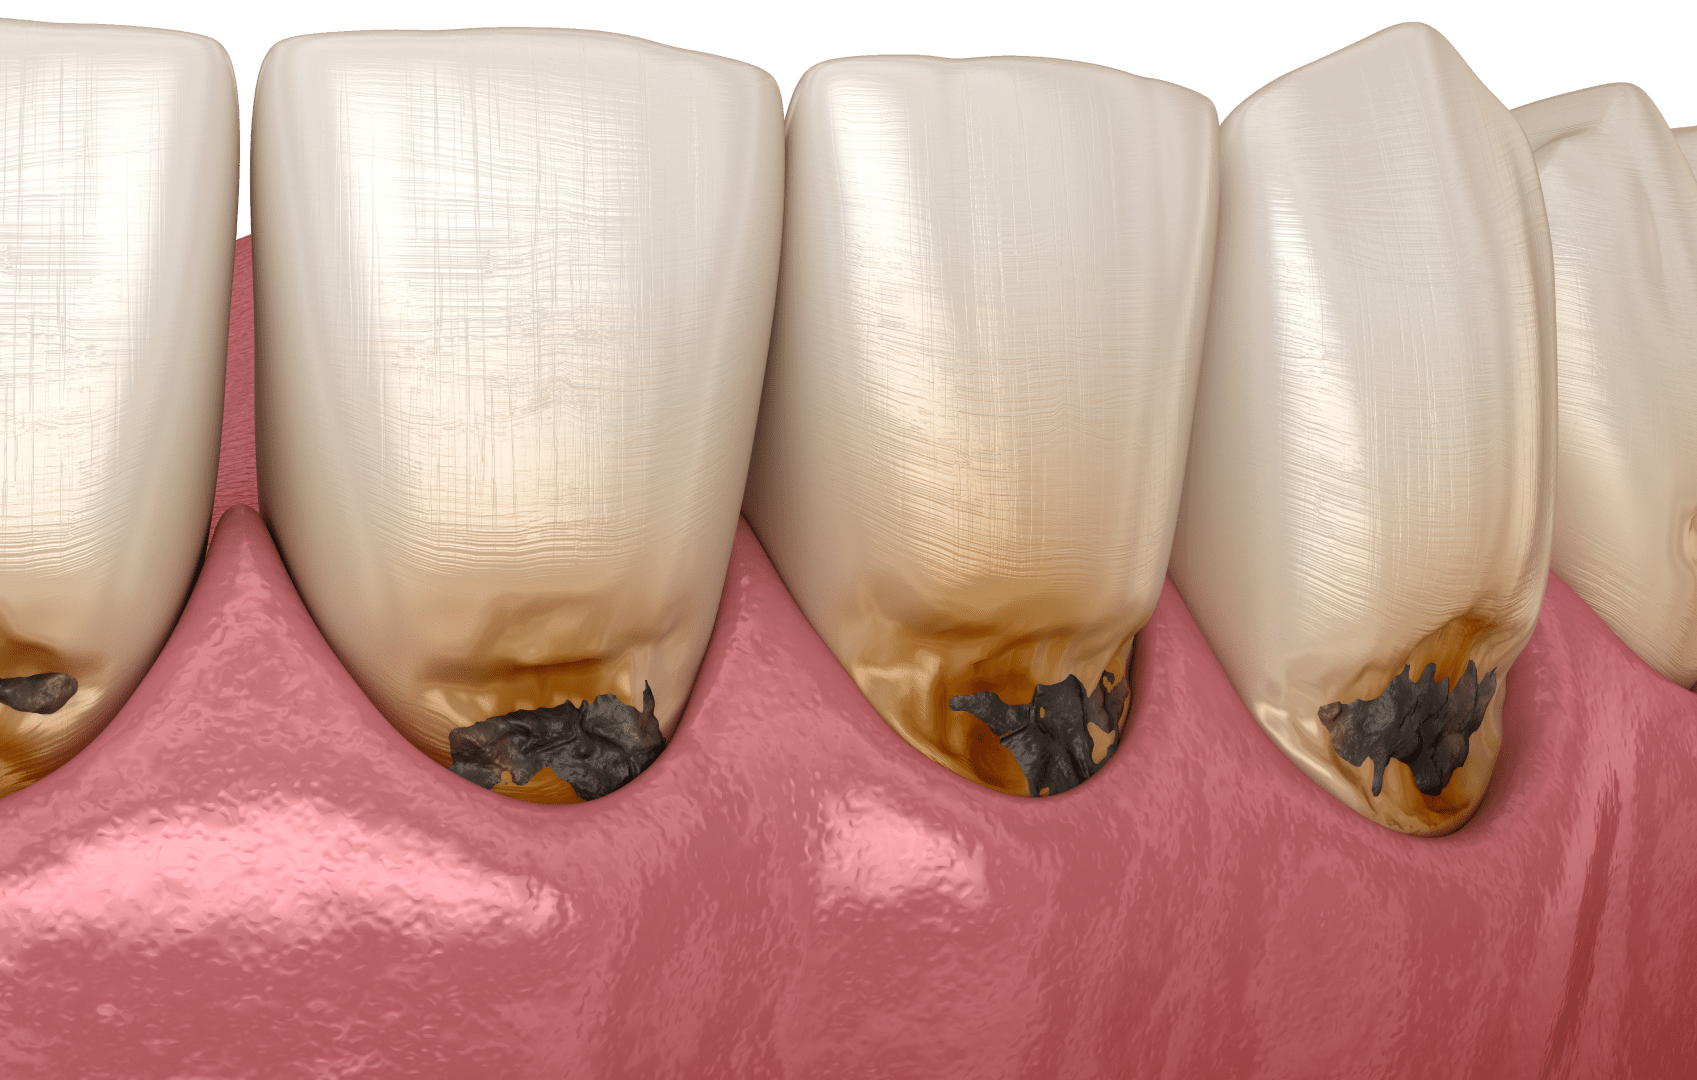

Як виглядає карієс на зубах? На початкових стадіях він проявляється як невелика біла або матова пляма на поверхні емалі. У міру розвитку захворювання вона темніє, з’являються коричневі або чорні ділянки. Поступово в зубі формується каріозна порожнина, яка може збільшуватися в розмірах.

Варто зауважити, що не всі темні плями на зубах є каріозними ураженнями. Як відрізнити карієс від пігментації та каменя? Пігментація зазвичай з’являється через вживання кави, чаю, вина або куріння і виглядає як рівномірне потемніння поверхні зуба без руйнування його емалі. Зубний камінь — це тверді відкладення мінералізованого нальоту, які найчастіше утворюються біля ясен і мають жовтуватий або коричневий колір. На відміну від карієсу, вони не утворюють порожнини в зубі.

На стадії поверхневого карієсу починається руйнування емалі. У місці, де раніше була світла пляма, поверхня зуба стає шорсткою, можуть з’являтися темні ділянки. У деяких випадках пацієнт починає відчувати підвищену чутливість зубів до холодної, гарячої або солодкої їжі.

На цій стадії розвитку карієсу захворювання поширюється глибше та уражає дентин — тканину, що розташована під емаллю. У зубі формується каріозна порожнина, яка поступово збільшується. У пацієнта може з’являтися дискомфорт під час жування, підвищена чутливість або періодичний біль.